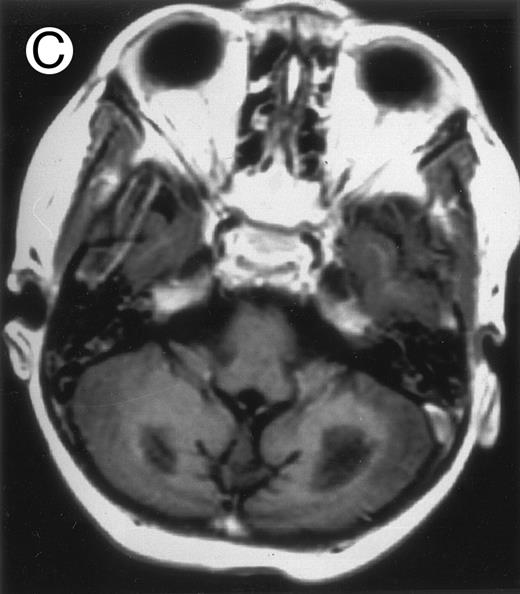

Among the nine children with initial neurological symptoms, seizures were the most frequent initial symptom in the youngest patients, whereas ataxia was found in the two oldest patients (46 and 58 months old, respectively) (Table 1). All nine patients had the same CSF abnormalities as patients with meningitis only. Eight of these nine patients had a neuroradiological study performed at the time of their first neurological symptoms (Table 1). The two most frequent lesions were focal necrosis with parenchymal volume loss and atrophy (Fig 2A and C) and white matter abnormalities (Fig 2B). Several small focal lesions with hypersignal at MR imaging that enhanced after administration of gadopentate dimeglumine (or contrast on CT scan) were also observed in two cases.

Three different aspects of brain imaging in HLH patients. (A) CT scan of a 3-month-old baby showing a large subdural effusion, several necrotic areas and hypodensities of the white matter. (B) Brain magnetic resonance of a 14-month-old boy showing large confluent areas of hypersignal in T2-weighted images. (C) Large symmetrical necrotic areas of cerebellar white matter in a 41/2-year-old girl (MRI).

Together, 19 patients had primary severe CNS disease progression or CNS relapse (Fig 1). Three of 19 had a CNS relapse characterized by meningitis only. Neurological symptoms occurred in 16 of these 19 patients (9 from the onset and 7 after the initial meningitis) (Fig 1). No clinical or neuroradiological difference was detected between the patients who developed neurological symptoms as the initial CNS manifestation or after initial meningitis (Table 1). The occurrence of these neurological manifestations marked a turning point in the evolution of the disease, as chemotherapy led to an improvement of the neurological symptoms in only three patients despite the use of intensive treatment by MTX IT. In these three patients, neurological sequelae persisted after the first symptoms and a relapse occurred within 3 to 10 months. Brain imaging was repeated during chemotherapy for four patients with progression of the CNS disease: in three patients, a severe brain atrophy developed (Fig 3A and B) and in the last patient who initially had contrast enhancement in cerebellar white matter, a cerebellum parenchymal loss was observed (Fig 2C). All of these 19 patients treated by chemotherapy only (n = 15) died during a last episode of coma and brain stem symptoms associated with a systemic hemophagocytic syndrome, 6 ± 6 months after the first neurological symptom (irrespective of the age at this first event). Four of these 19 patients were transplanted (one patient received an HLA-identical BMT, three an HLA-partially identical BMT). Median delay between diagnosis and BMT was 14 months (range, 2 to 20 months). All of these four patients died of BMT-related toxicity and/or disease progression.